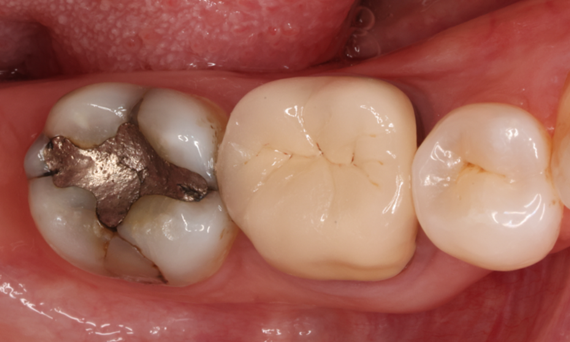

A lower second molar with sensitivity presented with cracks as well as an extensive Class I composite restoration on the buccal surface. According to the minimally invasive concept a CAD/CAM partial crown was planned, fabricated and bonded using CEREC Tessera in a single visit.

Before: Failed amalgam restoration needing replacement. Patient complaining of sensitivity and tooth presenting multiple cracks.